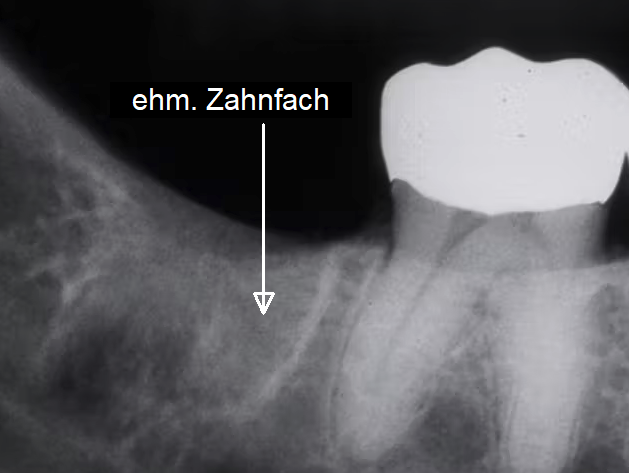

Es kann also vorkommen dass diese Ausheilungsprozesse im Kiefer nicht so ideal ablaufen und auf einer Röntgenaufnahme bei einer Routineuntersuchung möglicherweise noch den Umriss des nicht ausgeheiltem Zahnfachs zu sehen ist.

Diese Zahnfächer können bei einer Untersuchung hohl oder mit dichtem Narbengewebe oder mit noch nicht ausgereiftem Knochen gefüllt sein.